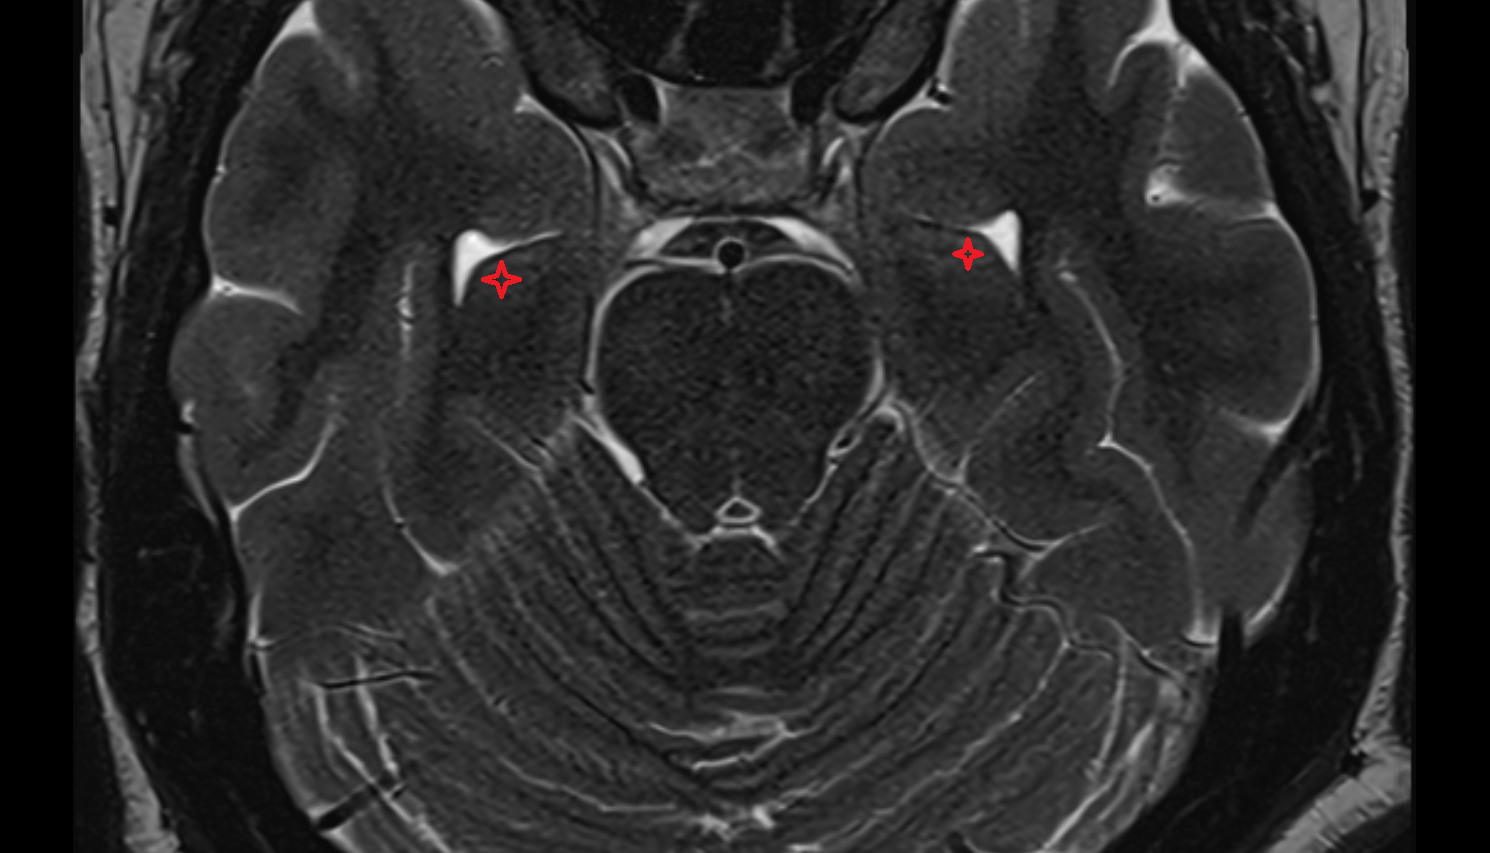

- Lateral aperture of fourth ventricle (foramen of Luschka)